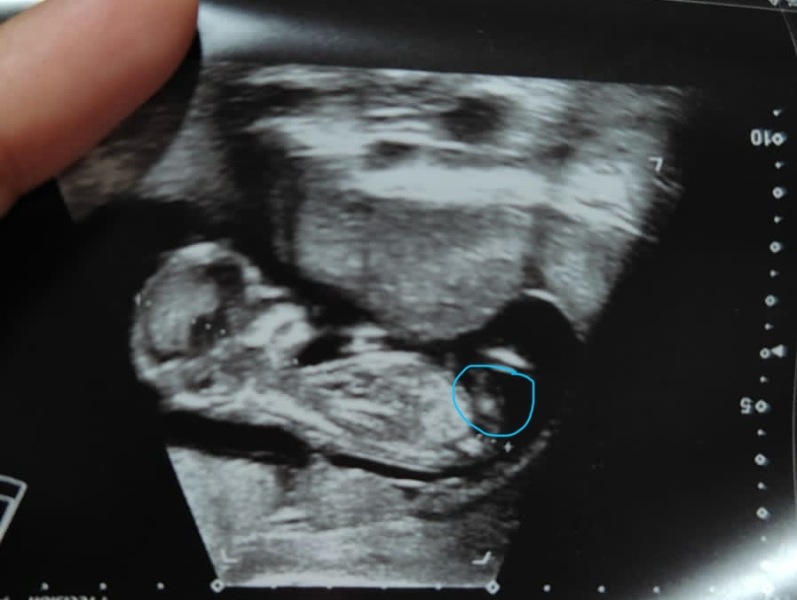

You think that’s the nub (circled in blue)?

Is this a nub?